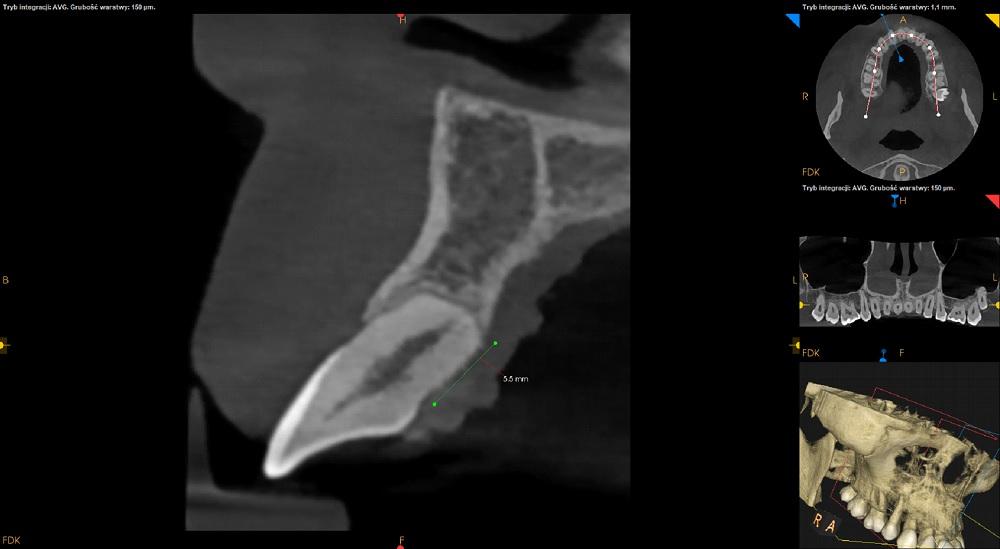

Resorpcja korzeni zębow przednich po leczeniu ortodontycznym

Resorpcja korzeni zębów 13-23.

Resorpcja korzeni zębów 33-43.